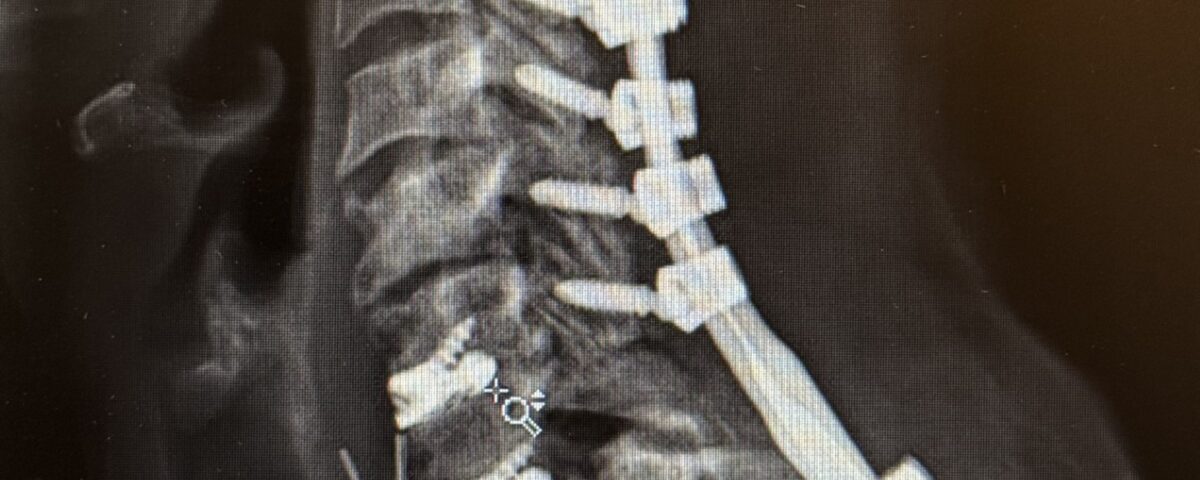

The patient is a 61-year-old female with a history of rheumatoid arthritis. She is 2-1/2-years status post C3-C7 laminectomy with posterior instrumentation and fusion. This procedure was performed to treat multilevel disc herniations with spinal cord compression following a motor vehicle accident.

She did well for several years, but then developed new onset of intractable neck pain with radiation to both upper extremities. She also had difficulty holding her head up.

Her rheumatologist ordered an x-ray which showed anterolisthesis of C7-T-1 with kyphosis and instability (Fig 1 right).